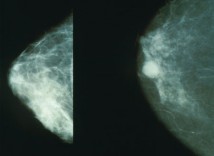

Рак дојке

Студија Journal of the National Cancer Института у 1994. години изведена на 1800 жена открила је да жене које су направиле побачај имају 50% повећану шансу да добију рак дојке прије 45. године живота. Дјевојкама које направе побачај прије 18. године живота ризик се повећава за 150%. Ако се побачај направи након 30. године живота ризик расте за 110%. Ако жена има у породици рак дојке ризик јој се повећава за 270% након 30. године живота. Свих 12 дјевојака млађих од 18 година које су судјеловале у истраживању и које су имале рак дојке у породици добиле су рак прије 45. године. Могућност добијања рака дојке још се више повећава ако жена направи више од једног побачаја.(1)

Мамограм дојке